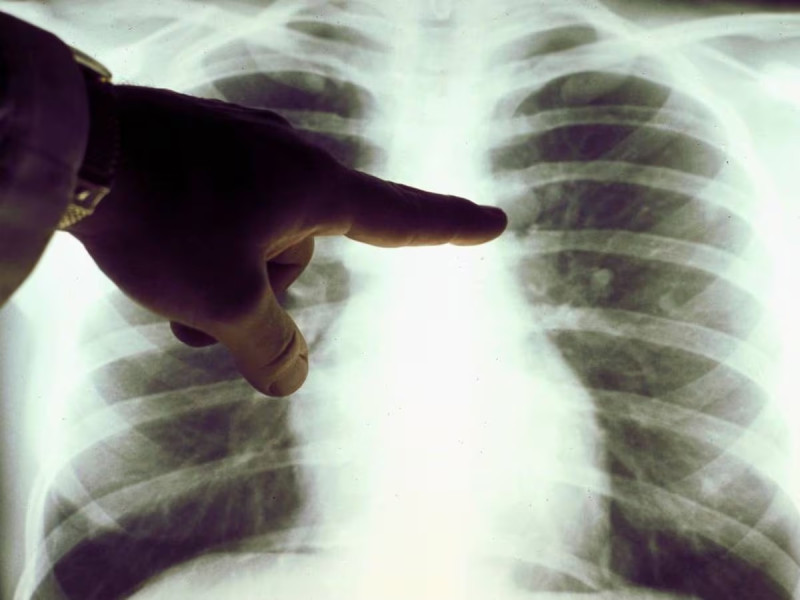

Un equipo de investigadores ha demostrado que la contaminación atmosférica está estrechamente relacionada con el mismo tipo de mutaciones del ADN que se asocian al tabaquismo, unas alteraciones que los científicos han hallado en mayor medida en personas no fumadoras con cáncer de pulmón, concluyendo que la polución es una de las causas de desarrollo de la enfermedad en esta población.

Secuenciando el genoma completo de 871 pacientes no fumadores, los investigadores identificaron distintos patrones de mutaciones del ADN, conocidos como firmas mutacionales, relacionados con exposiciones ambientales pasadas. Estos datos los combinaron con estimaciones de la contaminación atmosférica de cada una de las regiones en las que vivían los participantes del estudio.

Así, descubrieron que aquellos que vivían en entornos más contaminados presentaban un número significativamente mayor de mutaciones en sus tumores de pulmón. De hecho, estas personas presentaban 3,9 veces más mutaciones relacionadas con el tabaquismo y un 76 por ciento más de mutaciones relacionadas con el envejecimiento.

Los investigadores también observaron que cuanta más expuesta estaba una persona a la contaminación del aire, más mutaciones había en su cáncer de pulmón. También presentaban telómeros más cortos -los capuchones protectores de los extremos de los cromosomas-, un signo de envejecimiento celular acelerado.